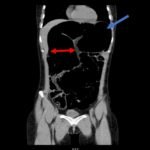

Computed tomography (CT) of the abdomen and pelvis was obtained revealing a colonic volvulus in the left mid to upper abdomen (blue arrow) involving the distal transverse colon and descending colon, with gaseous colonic distention to 8.5 cm (red arrow). The characteristic “whirl pattern” is also present (yellow arrow). These findings are suggestive of a high-grade colonic obstruction. It was without evidence of pneumoperitoneum, pneumatosis, or drainable collection. Of note, a 3.6 cm dermoid tumor is also observable in the left adnexa (green arrow).

Patients with sigmoid volvulus present with slow onset and progressive abdominal pain, nausea, abdominal distention, and constipation. Vomiting is also common but normally occurs several days after the initial onset of pain.5 Computed tomography is the preferred method of diagnosis with a sensitivity of 71%.6 Diagnostic findings include a “whirl pattern,” which is caused by the twisting of the sigmoid colon around its mesocolon, and a “bird-beak” appearance of the afferent and efferent colonic segments.7 Treatment of a sigmoid volvulus begins with a flexible sigmoidoscopy for decompression and detorsion, followed by definitive surgery to prevent recurrence.4 Without definitive surgery, recurrence rates of sigmoid volvulus has been reported as high as 90%.1 In this case, gastroenterology was consulted and patient was taken to the endoscopy suite for decompression and detorsion.